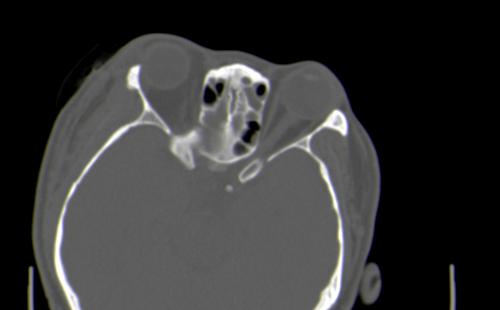

以下是引用皎皎白驹在2006-11-29 8:48:00的发言:[br]影像表现:双侧筛窦和上颌窦、鼻腔内均密度增高,右侧视神经增粗、弯曲,左筛窦顶部筛板及右侧纸板近视神经孔区可见骨折线。[br]结合临床表现考虑:右侧筛窦纸板近视神经孔区骨折致右侧视神经损伤。最好做个眼眶冠状扫描,更明确右侧视神经管是否狭窄。

以下是引用w_jianhua在2006-11-29 10:07:00的发言:[br]影像表现:双侧筛窦和上颌窦、鼻腔内均密度增高,右侧视神经增粗、弯曲,左筛窦顶部筛板及右侧纸板近视神经孔区可见骨折线。[br]结合临床表现考虑:右侧筛窦纸板近视神经孔区骨折致右侧视神经损伤。最好做个眼眶冠状扫描,更明确右侧视神经管是否狭窄。 [br] [br]支持[br]